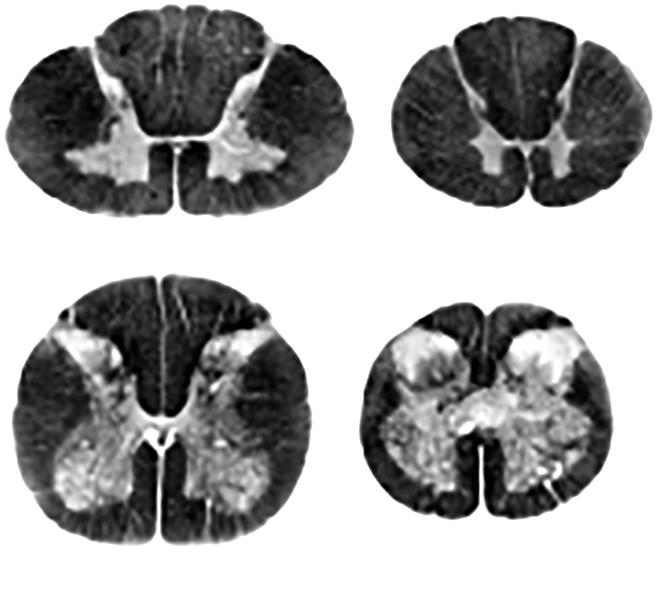

дити діагностування онкологічного захворювання (іл. 7). Цитологічні методи вивчення будови клітин уможливлюють виявлення спадкових захворювань, наприклад пов’язаних зі зміною кількості хромосом (як-от синдром Дауна). Мікробіологічні методи дозволяють виділити з організму й розпізнати збудників деяких інфекційних хвороб.

Зміни в будові внутрішніх

хірургічного втручання, застосувавши

випромінювання (іл. 8). Його використання є

(КТ), яка дозволяє отримувати тривимірні зображення органів. Ще більші можливості дає магнітно-резонансна томографія (МРТ). Низка методів скерована на вивчення функціонування внутрішніх органів: електрокардіографія реєструє електричну активність серця, електроенцефалографія головного мозку, спірометрія оцінює параметри дихання. Побачити внутрішні порожнини (шлунка, кишки) можна за допомогою тонких пристроїв з оптичними зондами ендоскопів.